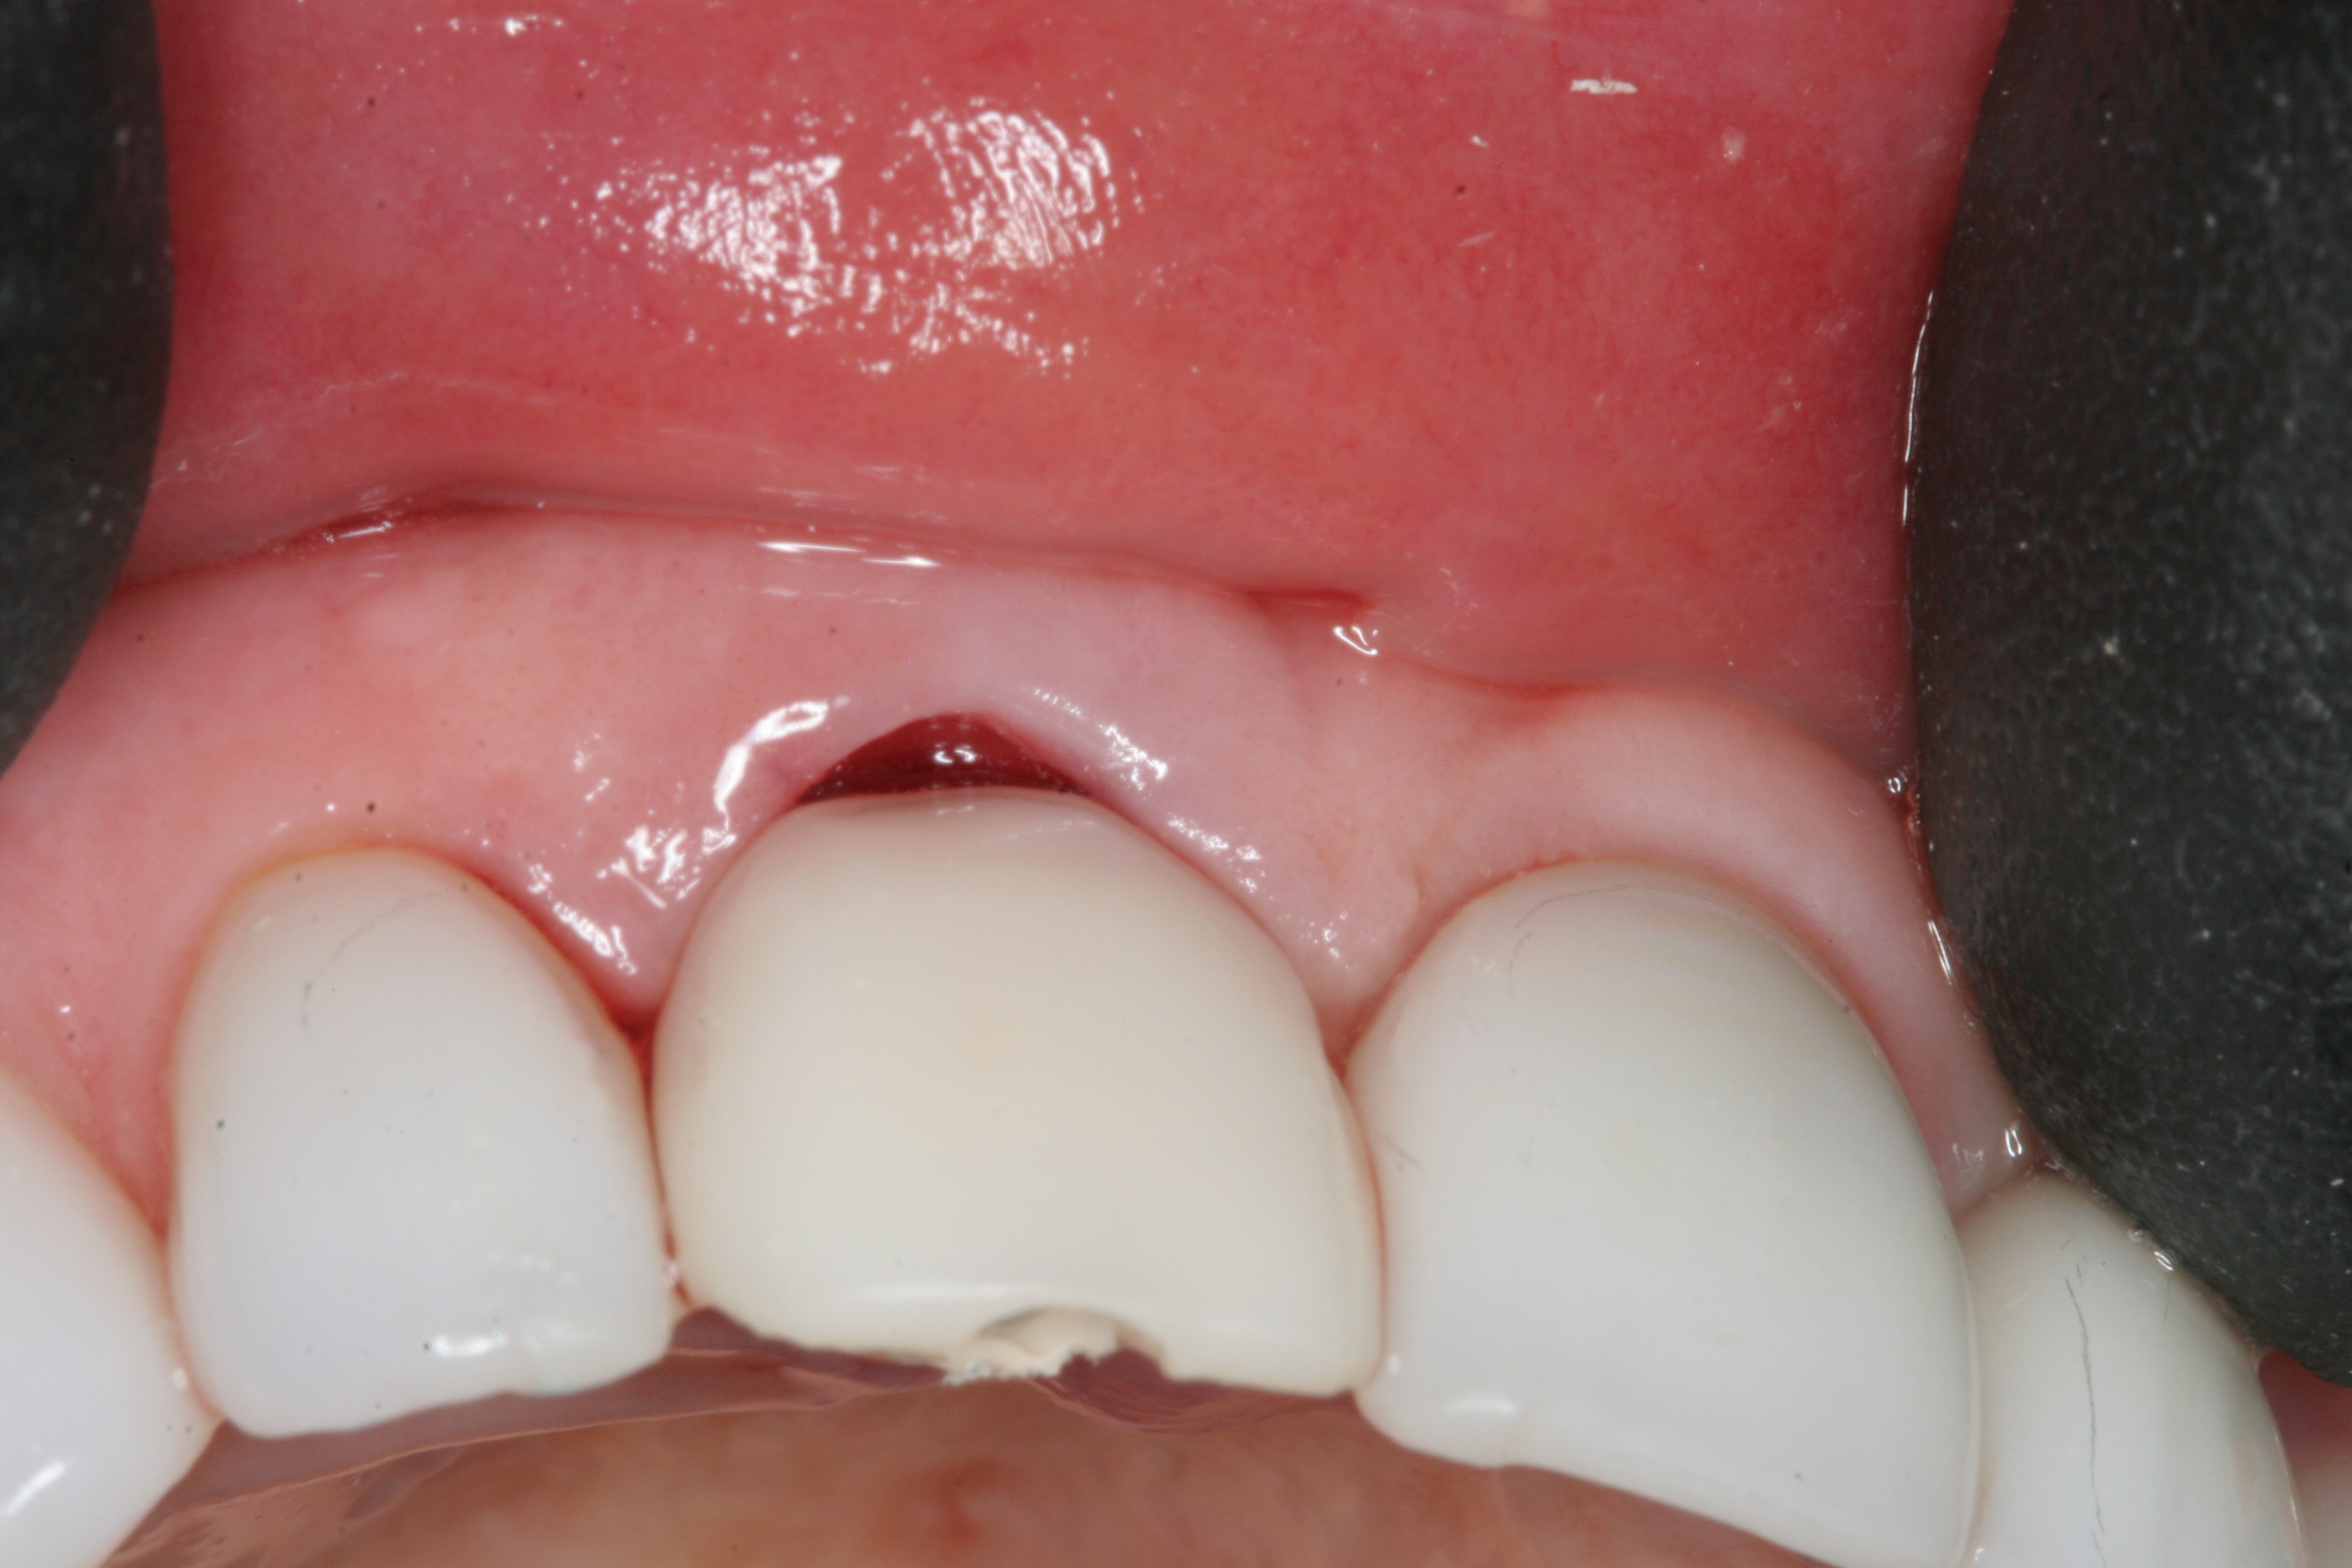

Fig 1. Preoperative clinical photograph of fractured maxillary right central incisor (tooth No. 8).

Figure 1

A 63-year-old female patient presented with mobility of her right maxillary incisor, tooth No. 8, secondary to endodontic therapy (Figure 1). Her medical and dental histories were non-contributory. Clinical and radiographic evaluations revealed an 8-mm probing depth on the palatal aspect. The tooth was deemed to be fractured (Figure 2). The treatment plan accepted by the patient was for extraction, immediate implant placement, and immediate provisional restoration, if possible.